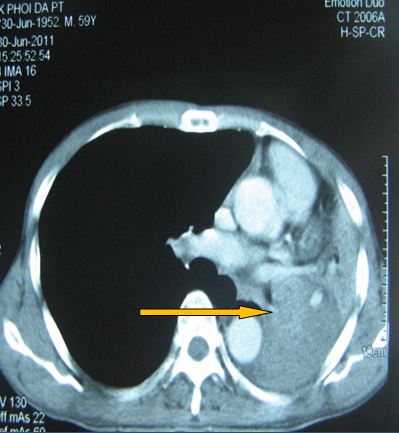

-          Bệnh nhân được tiến hành chụp cắt lớp vi tính ngực (CT ngực) đánh giá: có hình ảnh tổn thương toàn bộ thùy trên phổi trái

Hình ảnh tổn thương tái phát tương ứng với thùy trên phổi trái

Trước điều trị

Tổn thương ở vị trí thuỳ trên phổi trái: khối đông đặc và tổ chức u